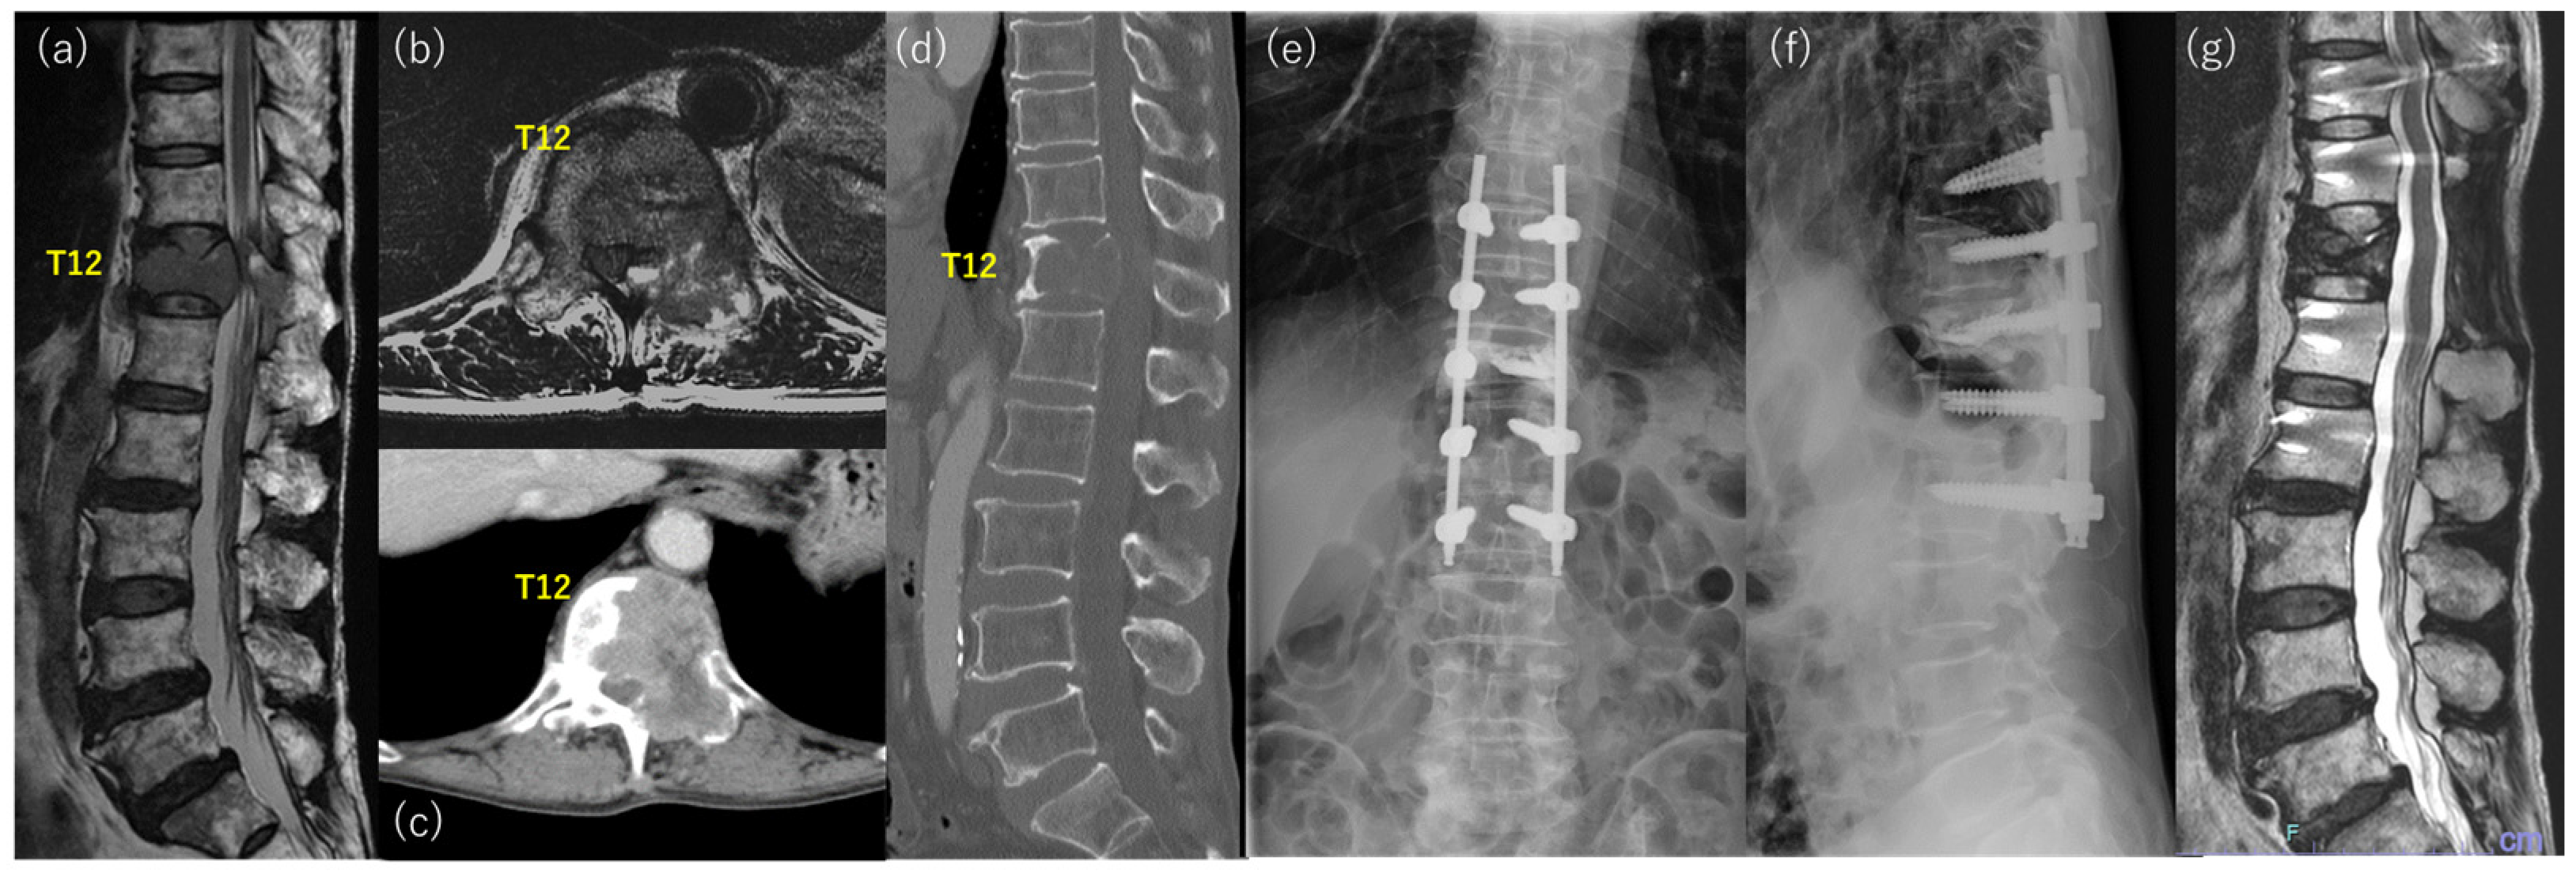

Primary Osseous Malignancies of the Spine。Thoracic spine metastases from lung cancer with incomplete。Frontiers | Stevens–Johnson syndrome induced by toripalimab。「WHO Classification of Tumours, 5th ed., Vol.5」著者: WHO Classification of Tumours Editorial Board出版社: WORLD HEALTH ORGANIZATIONISBN: 978-92-832-4506-3ページ数: 565pp.出版年: 2021年定価 :23.550円(税抜)裁断済みです。診察ができる vol.1 身体診察。Risk Factors for Poor Outcome after Palliative Surgery for。汚れはありません。